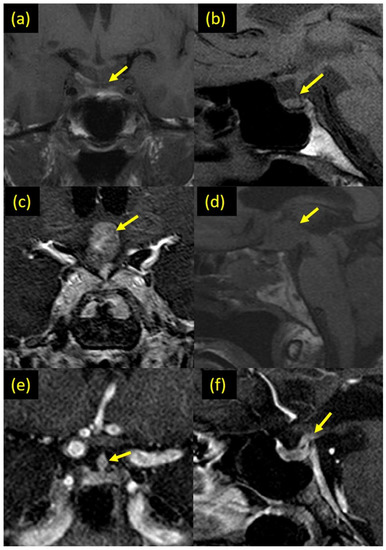

3.1. Types of Abnormal Pituitary Imaging

| Thickened pituitary stalk | 15 (24.6%) |

| Abnormal enhancement | 11 (18.0%) |

| Suprasellar mass | 2 (3.3%) |

| Loss of the posterior pituitary bright spot | 22 (36.1%) |

| Small pituitary | 9 (14.8%) |

| Stalk deviation | 7 (11.5%) |

| Pituitary encasement | 3 (4.9%) |

| Empty sella | |

| Complete | 3 (4.9%) |

| Partial | 4 (6.6%) |

| Microadenoma | 1 (1.6%) |

| Pars Intermedia cyst (incidental finding) | 3 (4.9%) |

| Rathke’s cyst (incidental finding) | 1 (1.6%) |